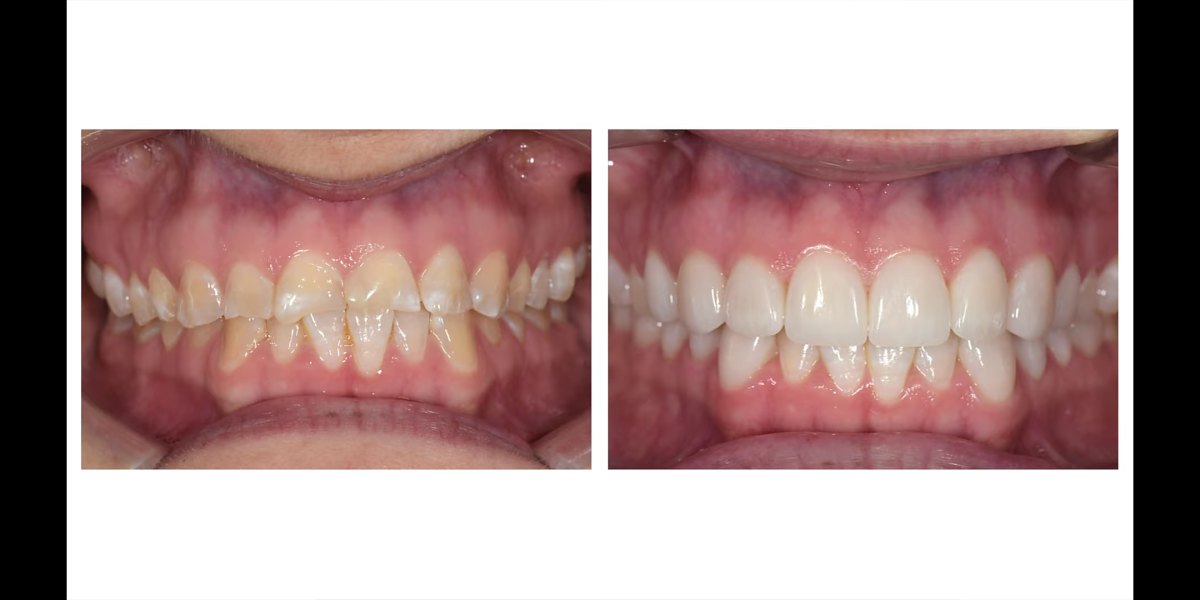

Starte zęby są coraz częstszym problemem dotykającym naszych pacjentów – jego rozwiązaniem jest odbudowa, którą wykonujemy w naszej klinice w Lublinie.

Starcie polega na zmniejszeniu grubości, a w konsekwencji utracie zewnętrznych warstw tkanek. Każdy z nas w ciągu swojego życia ściera zęby. Jednakże niestety coraz częściej pojawia się problem uogólnionego patologicznego ścierania. Dotyczy on często młodych ludzi i prowadzi nie tylko do problemów estetycznych, ale również zaburza funkcję żucia. Stwarza również inne dolegliwości: wzmożoną wrażliwość na zimne, gorące i kwaśne pokarmy, przebarwianie się uzębienia. Stają się ostre, kaleczą tkanki miękkie. Na skutek zmniejszenia wysokości zwarcia pojawiają się problemy w stawie skroniowo-żuchwowym, często ból w okolicy uszu, twarzy. Wszystko to sprawia, że konieczna jest odbudowa zęba, którą wykonujemy w naszej klinice w Lublinie.

Co więcej, starty ząb powoduje również zakłócenie w obszarze estetyki. Uzębienie o nierównych kształtach czy nieregularna linia zgryzu zaburza symetrię uśmiechu. A jeśli zęby zostały już bardzo mocno starte, między nimi mogą tworzyć się nieestetyczne szczeliny. Taka sytuacja powoduje obniżony poziom samooceny, kompleksy w obrębie uzębienia czy ogranicza pewność siebie w trakcie nawiązywania kontaktu z innymi.

Ponadto odbudowa zęba w Lublinie to opłacalny krok pod względem przyszłości. Inwestycja w tę procedurę stomatologiczną sprawi, że uzębienie będzie mocniejsze i trwalsze. Nasi specjaliści wykorzystują niezwykle wytrzymałe materiały, dzięki czemu odbudowane zęby stają się odporniejsze na działanie czynników, które dotychczas przyczyniały się do ich ścierania. To sprawia, że problem zostaje rozwiązany, a uzębienie zachowa swój piękny, zdrowy wygląd przez wiele kolejnych lat.